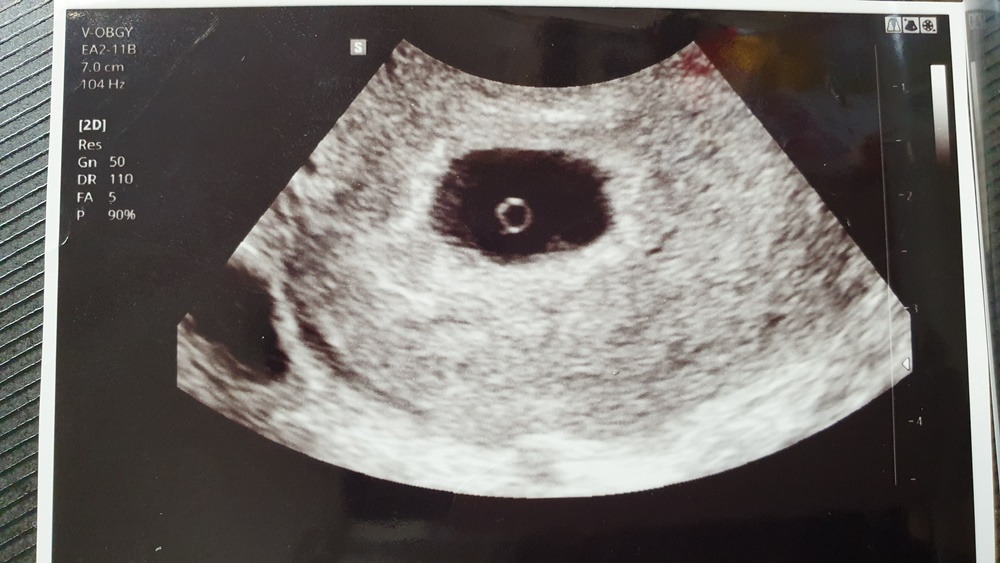

4932_11635_3724.jpg 임산부의 초음파 사진. 동그란 부분이 아기집이라고 한다. 나도 언젠가 이런 사진을 받을 수 있겠지.